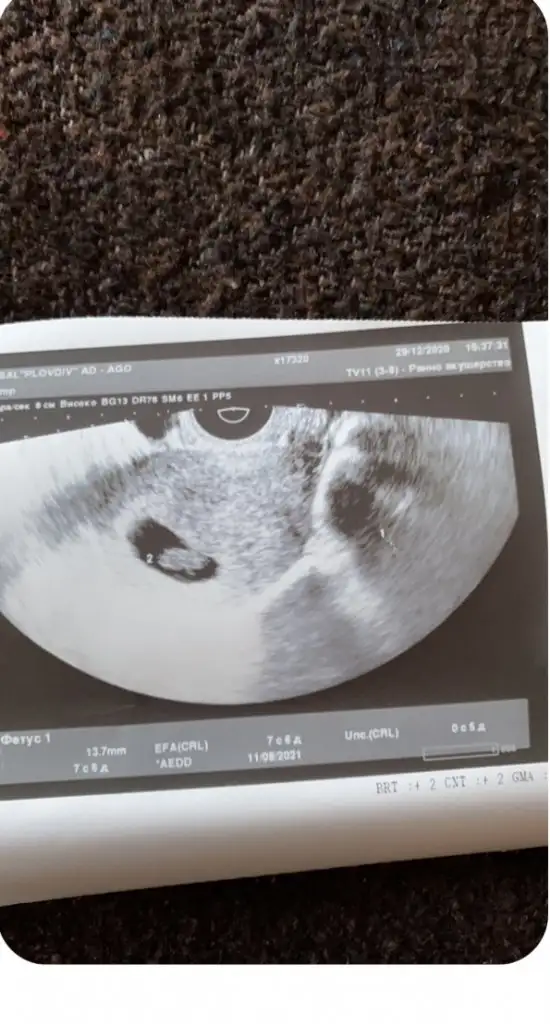

Kiz erkek aslinda fark etmiyor ama yavrumu severken ona kizim ya da oglum demek icin merak ediyorum 🥰😘